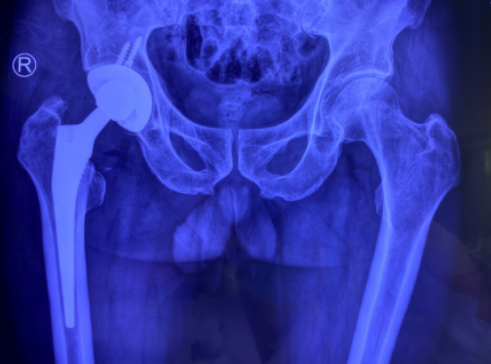

术后

完善相关检查后,邱东新副主任医师团队联合麻醉科会诊,制定了最优化的麻醉及手术方案,保证手术细节的完善周全。随后,手术团队给许大爷进行了右人工全髋关节置换术,手术进行了1个半小时,顺利完成。术后,老人被送回关节病区康复。此后,老人的康复速度很快,第2天就下床在助行器帮助下行走,第3天就不用助行器行走了,术后5天出院。